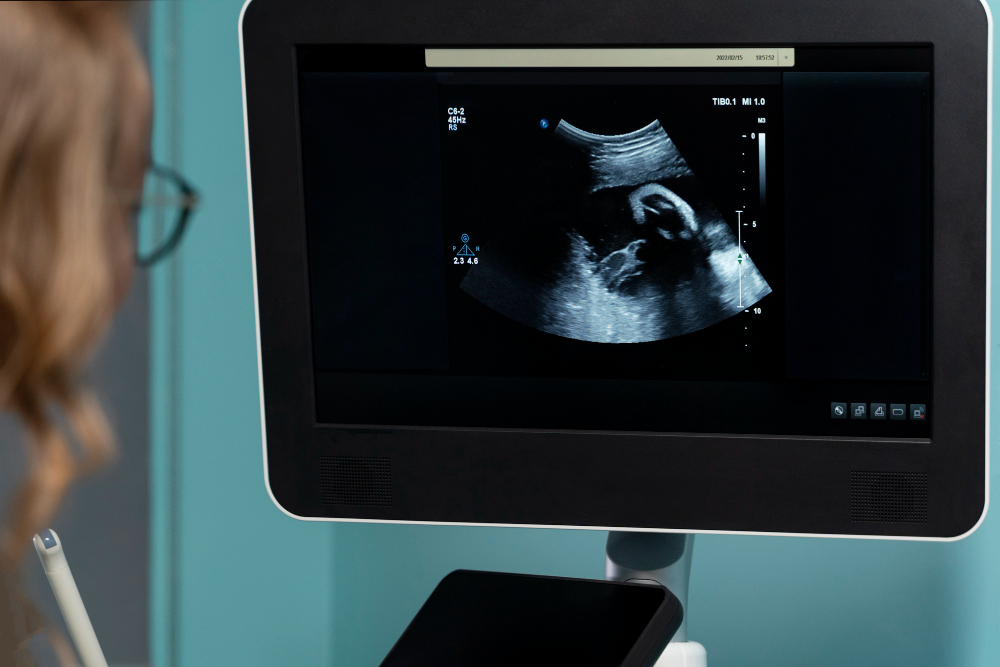

NT Scan: What It Is, Why It’s Done, and What to Expect

What is an NT Scan? An NT Scan, or Nuchal Translucency Scan, is a special ultrasound done during pregnancy. Doctors use this test to check